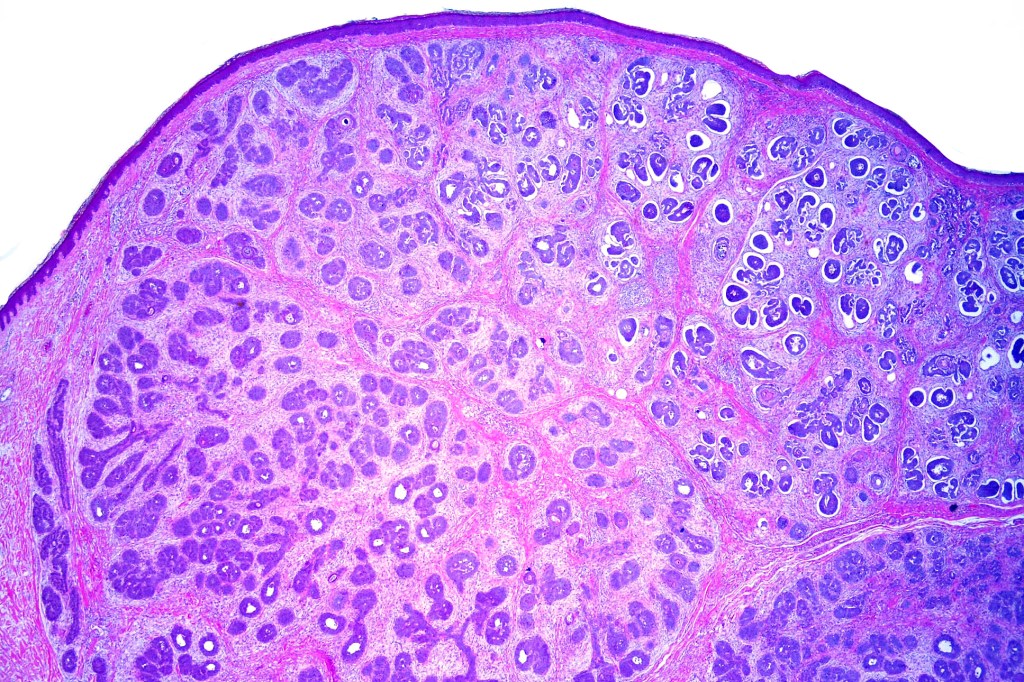

•Sharply circumscribed, unencapsulated nodule in deep dermis +/- subcutaneous fat or deeper (trichoepithelioma is much more superficial)

•Variably sized but generally large, basophilic tumor nodules composed of small uniform basaloid cells with minimal cytoplasm

•Peripheral palisading but no retraction artifact or stromal mucin deposition

•Variants include cystic, rippled pattern, pigmented, clear cell, trichoblastoma with ductal differentiation & trichoblastoma with sebaceous differentiation